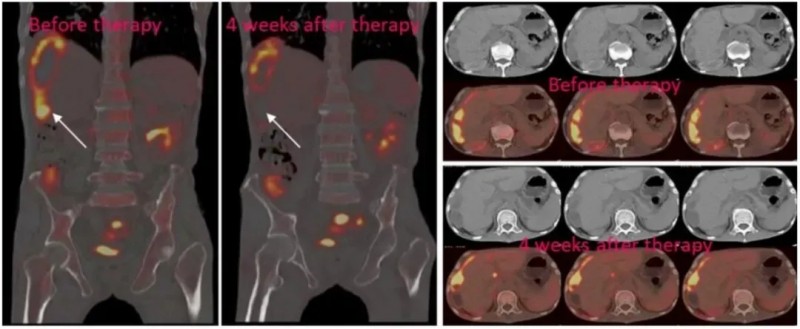

结果显示:2例患者经腹腔输注低剂量CAR-NK细胞后,腹水生成速度显著减缓,腹水中的肿瘤细胞数量急剧下降;另1例伴肝转移的患者采用“腹腔灌注联合超声引导下瘤内注射”方案治疗后,PET-CT检查提示肝脏病灶实现完全代谢缓解(详见下图)。值得关注的是,3例患者在治疗全程均未出现3级及以上不良反应。

▼3号患者经NKG2D CAR-NK治疗后,肝转移病灶的PEC-CT对比